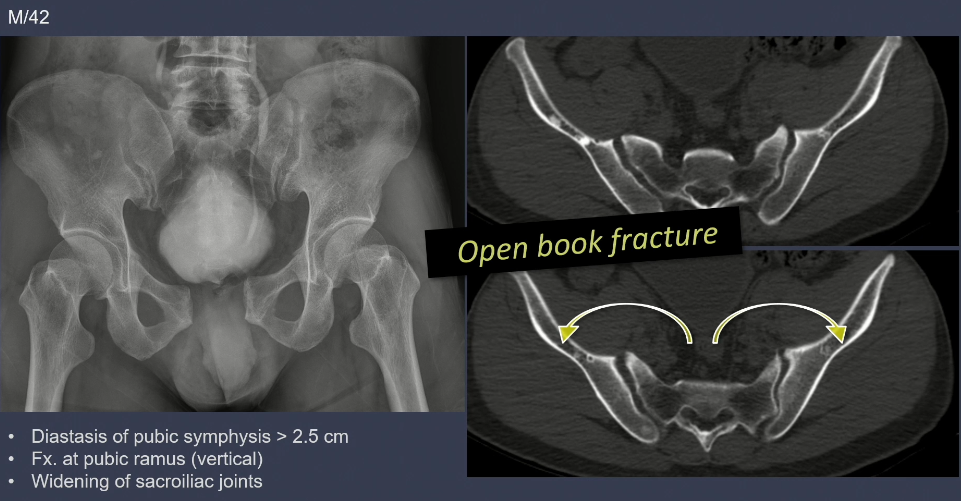

2. APC type